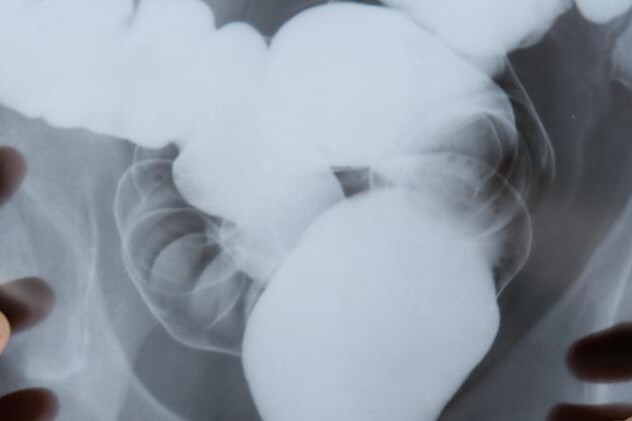

Diagnostika ulcerózní kolitidy spočívá ve vyšetření stolice, aby se vyloučila bakteriální, virová či parazitární příčina průjmů. Pro stanovení diagnózy ulcerózní kolitidy jsou důležité endoskopické metody. Pacient bývá indikován ke kolonoskopii, což je endoskopické vyšetření tlustého střeva pomocí kolonoskopu. To je dlouhá hadice, která má na svém konci sondu s kamerou, kterou lékař zavede konečníkem do tlustého střeva. Druhým koncem hadice může lékař ovládat kolonoskop. Při tomto vyšetření má lékař vizuální náhled na střevo a pátrá po případných změnách. Další možností je rentgenové vyšetření s kontrastní látkou. V případě vyšetření tlustého střeva se kontrastní látka podává konečníkem, tzv. klyzma. Tato látka se v tlustém střevě zadrží po určitou dobu, během které rentgenové paprsky snímkují střevo. Toto vyšetření umožňuje odhalit známky zánětu ve sledované oblasti či změny reliéfu.